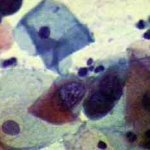

Πινακοθήκη κυτταρολογικών ευρημάτων ΙΙΙ

Οι πινακοθήκες κυτταρολογικών ευρημάτων, έχουν σαν στόχο να εμπλουτίσουν την κυτταρολογική εμπειρία σπουδαστών και ειδικευομένων, όπως ένας άτλαντας.

Παρουησιάζονται λοιπόν τυχαία ευρήματα, από το καθημερινό γυναικολογικό ιατρείο.